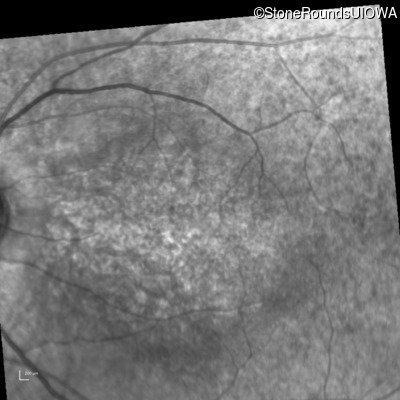

Infrared Fundus Photograph - Right - 10/200

Exemplar

Infrared Fundus Photograph - Left - 10/160 -1